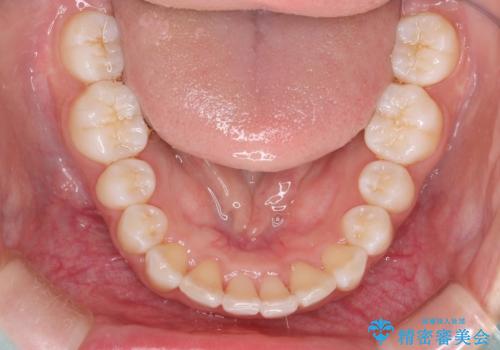

Invisalign インビザラインによる軽度なガタつきの改善

- 奥歯の位置関係はそこまで大きくいじらず、前歯群のみでガタつきの改善を計画しました

奥歯の位置関係に改善の余地はありますが、機能的に問題のない cusp to fossa の関係で咬めているため、前歯のガタつきを前歯のみで改善するというシンプルな計画で、短期間で治療を終了させました。